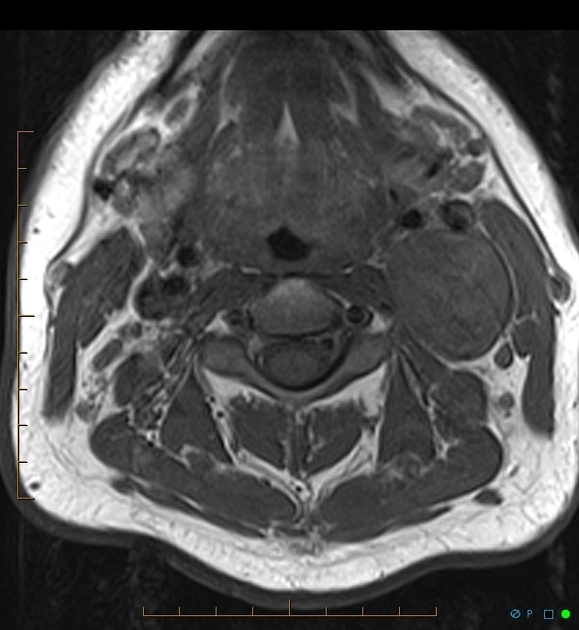

Schwannoma chuỗi giao cảm (Sympathetic Chain Schwannoma - SCSC)